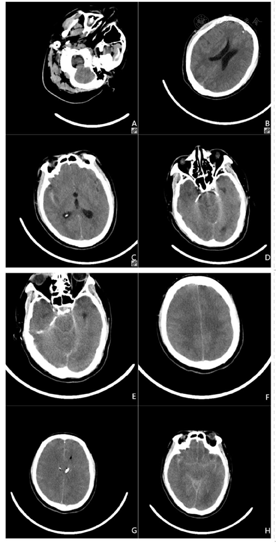

入院后分别行4次头颅CT及1次头颅CTA检查,见图1。

实验室检查方面,患者血常规中性粒细胞明显增多,感染指标CRP、PCT升高均与既往确诊病例类似而不具有特异性[12],不再赘述。需要注意的是,患者既往无糖尿病病史,但血糖、尿糖均高,结合后期出现尿崩,考虑为中枢神经系统受损导致,但具体机制目前仍不明确[12,13]。另外,患者CT表现进行性脑水肿及与侧裂高密度影[14],后经CTA检查排除脑血管相关性疾病,考虑阿米巴引起脑实质出血性炎症导致继发性蛛网膜下腔出血。这情况在陈宝建等[4]的报道中亦有提及。另外,由于福氏纳格里阿米巴可分泌蛋白酶、磷脂酶和穿孔素等,往往导致患者脑脊液中充满大量纤维脓性分泌物[7]。